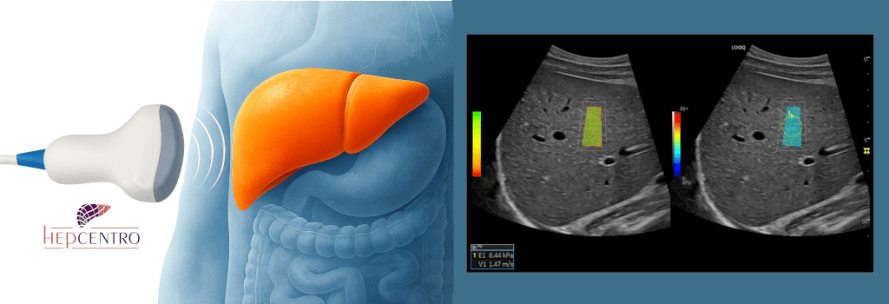

- Elastografia hepática (ou FibroScan®) — mede a rigidez hepática, estimando o grau de fibrose do fígado, a probabilidade de cirrose e de hipertensão portal.

- Ultrassonografia hepática — avalia morfologia e, se houver cirrose, é usada para rastreamento de carcinoma hepatocelular (CHC) a cada 6 meses.